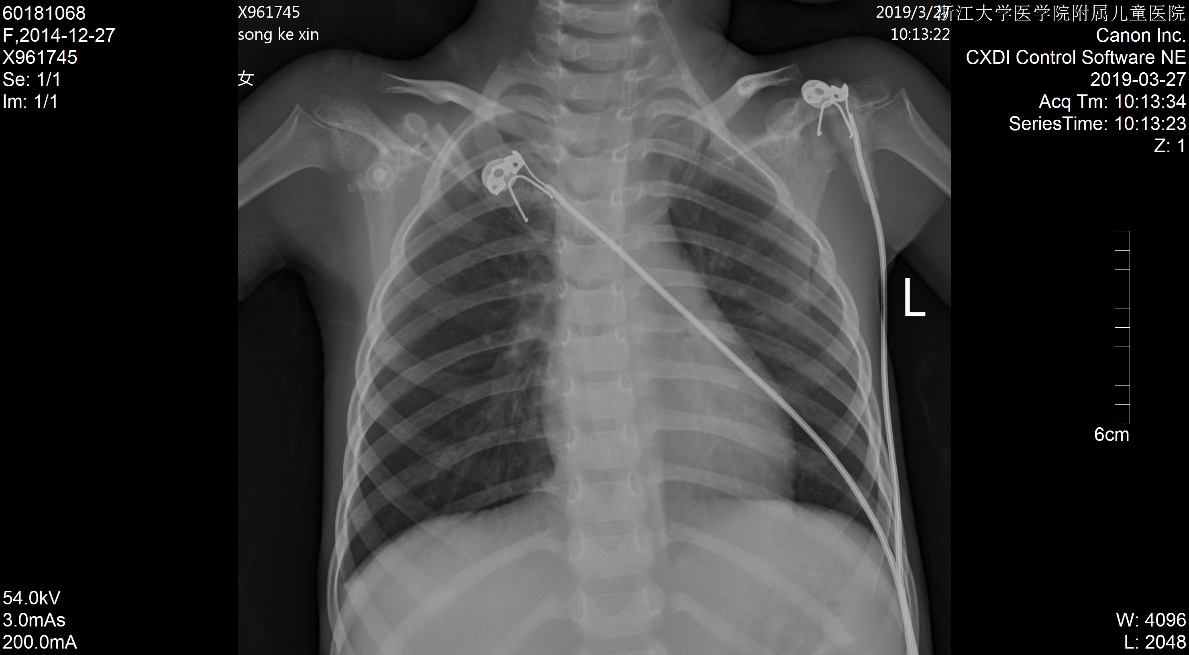

1 资料与方法患儿女,5岁2月,因“多尿、多饮、多食3个月余,意识不清1天余”由外院转入。3个月余前出现多尿、多饮、多食,家长未重视,未就诊。1 d前出现意识不清,并抽搐3次,急送当地医院就诊,当时查体情况具体不详,查血气电解质示pH 6.87,pCO225.9 mmHg,Na+ 125.4 mmol/L, Glu 17.1 mmol/L,Lac 1.1 mmol/L,HCO3- 4.6 mmol/L,ABE -28.1 mmol/L。考虑诊断“糖尿病、糖尿病酮症酸中毒、脑水肿?”收住当地医院。在当地医院住院期间,予大量补液[约3 L/24 h,大部分为晶体液,可能因为低血压,因住院期间曾使用多巴胺10 μg/(kg·min)维持],住院期间出现氧饱和度不能维持,遂予气管插管并机械辅助通气。因病情持续恶化,联系后转入本院PICU。既往史、个人史、出生史无殊。爷爷及外婆有糖尿病及高血压病。入院查体:T 37.8℃,脉搏:146次/min,呼吸:38次/min(为机械通气),血压98/77 mmHg(1 mmHg=0.133 kPa),无特殊面容及畸形,体质量:11 kg,气管插管带入,经皮血氧饱和度95%,镇静状态,双侧瞳孔等大等圆,直径2 mm,对光反射存在,颈软,余神经系统无明显阳性体征,面色苍白,消瘦貌,双肺呼吸音粗,可闻及湿啰音,腹软,肝脾肋下未及,皮肤弹性略差,肢端凉,毛细血管充盈时间5 s。入院后查白细胞计数8.52×109/ L-1,淋巴细胞15.4%,中性粒细胞82.0%,超敏C反应蛋白17.33 mg/L;血气分析:pH 6.996,pO2 91 mmHg, pCO2 43.5 mmHg,Na+ 126 mmol/L,Glu 21.0 mmol/L,Lac 2.9 mmol/ L,HCO3- 10.1 mmol/L,ABE -20.6 mmol/L;血氨63 μmol/ L;生化五类:总蛋白34.9 g/L,白蛋白26.5 g/L,丙氨酸氨基转移酶24 U/L,天门冬氨酸氨基转移酶96 U/L,肌酐147 μmol/L,尿素12.38 mmol/L,肌酸激酶1 680 U/L,肌酸激酶-MB活性166 U/L,甘油三酯6.05 mmol/L,胆固醇6.11 mmol/L,淀粉酶3 094.5 U/L;尿常规:尿酮体++,尿蛋白++,尿糖++++,尿隐血+++;糖化血红蛋白16.5%;血清C肽测定:0.116 nmol/L;糖尿病自身抗体阳性;脑脊液常规、生化及培养无殊;血尿培养阴性;胸片:两肺弥漫性病变,双侧胸腔积液,肺水肿待排(图 1);心超:左室收缩功能稍减低(EF 0.53),少量心包积液,二、三尖瓣轻度反流;腹部B超:肝大、腹腔积液。考虑诊断“急性呼吸窘迫综合征、急性肾功能损伤、1型糖尿病、糖尿病酮症酸中毒、脑水肿、多浆膜腔积液”,予呼吸机支持[HFO模式,FiO2:85%,f:5.8 HZ,ΔP:36 cmH2O(1 cmH2O=0.1 kPa),MAP:25 cmH2O, OI:23)、多巴胺及肾上腺素泵注维持血压、甘露醇降颅压、胰岛素注射降血糖及其他对症支持治疗,患儿入院第3天酮症酸中毒基本纠正,第6天改无创通气(CPAP,Flow:10 L/min,PEEP:4 cmH2O),入院第10天改大气吸入,复查胸片基本好转(图 2),住院期间未再抽搐,在停呼吸机机械通气镇静后意识好转,但较激惹、躁动,肾功能逐步恢复,住院28 d后出院,出院前患儿意识清,能完成日常对答,查头颅MRI提示脑萎缩改变,复查肺部影像学未出现遗留性病变,复查心超未见心包积液。现规律随访近一年,胰岛素治疗血糖控制尚可,未遗留明显神经系统、呼吸系统等后遗症。本研究经浙江大学医学院附属儿童医院伦理委员会批准(批准号:2020-IRB-078),并经患儿家属知情同意。

| 图 1 入院时胸片 |

本例患儿,既往没有慢性肺部疾病及心脏疾病的情况下,急性起病,并呈进行性低氧血症,伴X片改变,且心超不支持左心功能不全,虽有液体超负荷的病史,但经积极的限液利尿治疗,其氧合指数(OI)仍≥ 16,故诊断ARDS[3-4]。另曾有报道DKA合并纵膈气肿的[5],但本病例胸片未提示气肿。